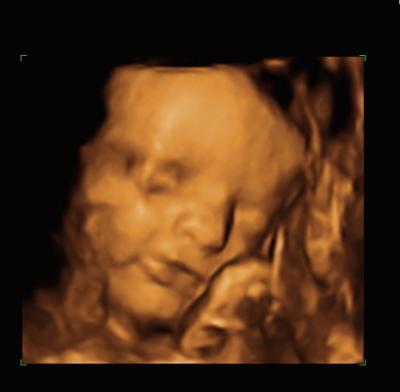

Mein kleiner hat in den letzten 3 Wochen ganze 900g zugenommen und wiegt jetzt schon 2kg. Kommt mir ganz schön schwer vor, hoffentlich geht das nicht so weiter denn wir haben noch 8 Wochen Beim CTG hat er wohl Schluckauf gehabt, total süß. Er hat sich auch schon mit dem Kopf nach unten gedreht. Mein Hb-Wert hat sich auch wieder normalisiert, hatte schon Angst weil ich die letzten Tage so blass bin. Hier noch ein Bild vom 3D Ultraschall was euch zeigen wollte

Bild zu heute wieder Termin gehabt + Bild - Forum für Januar - Mamis